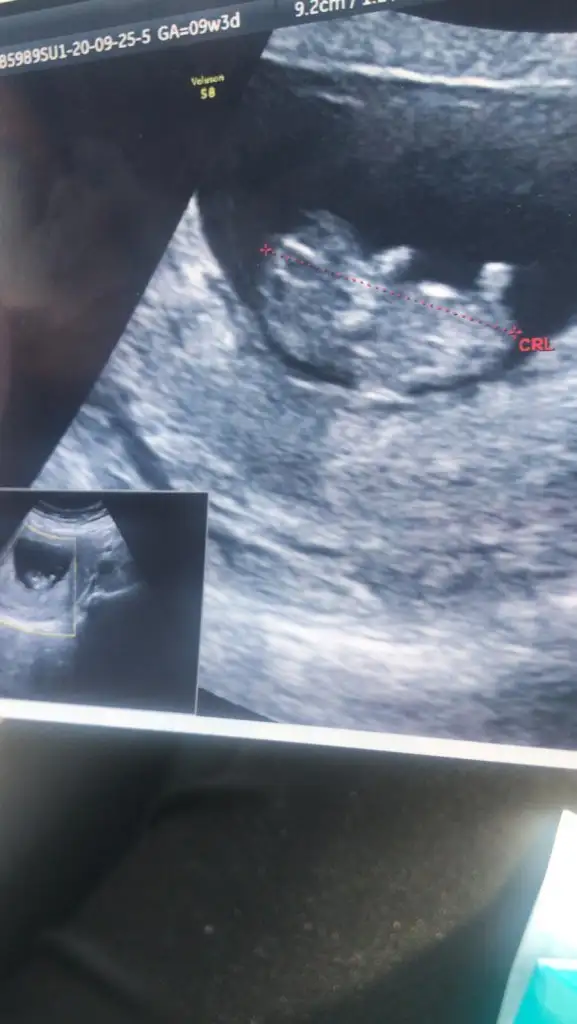

Kaç haftalık USG hiç net değil sanki Küçük nub için 11 12 13 haftalar olmalı

10+1 arkadaşımın da ☺Kaç haftalık USG hiç net değil sanki Küçük nub için 11 12 13 haftalar olmalı

Daha erken 11 12 13 haftalar olmalı şimdilik kız gibi ama istediğim haftalar olmalibu arkadaşımın 10 hafta şu an benimkini bildiniz hemen yollayım dedim o yüzden kız mı erkek mi

Tam dik değil paralelde değil yüzde verirsem sanki %70 kız gibi gibi başka usgde paylaşın 11 12 13 haftalar olmalıEki Görüntüle 2696428 bende tahmin alabilir miyim